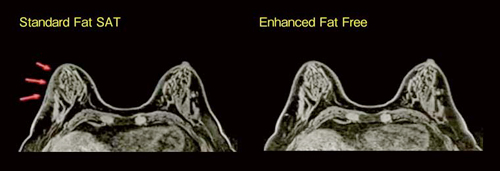

●Enhanced Fat Free:サブトラクション処理を不要にした脂肪抑制法(図2)

MRマンモグラフィでは,両側乳房に均一な脂肪抑制効果が必要となります。新たな脂肪抑制法である“Enhanced Fat Free”は,2種類の脂肪抑制パルスを組み合わせることで,人体が撮像領域に入ることで乱れてしまう磁場や,RFパルスの不均一性の影響を低減し,安定した脂肪抑制が可能となりました。

図2 Enhanced Fat Free

均一な脂肪抑制効果は,サブトラクション処理を不要にします。